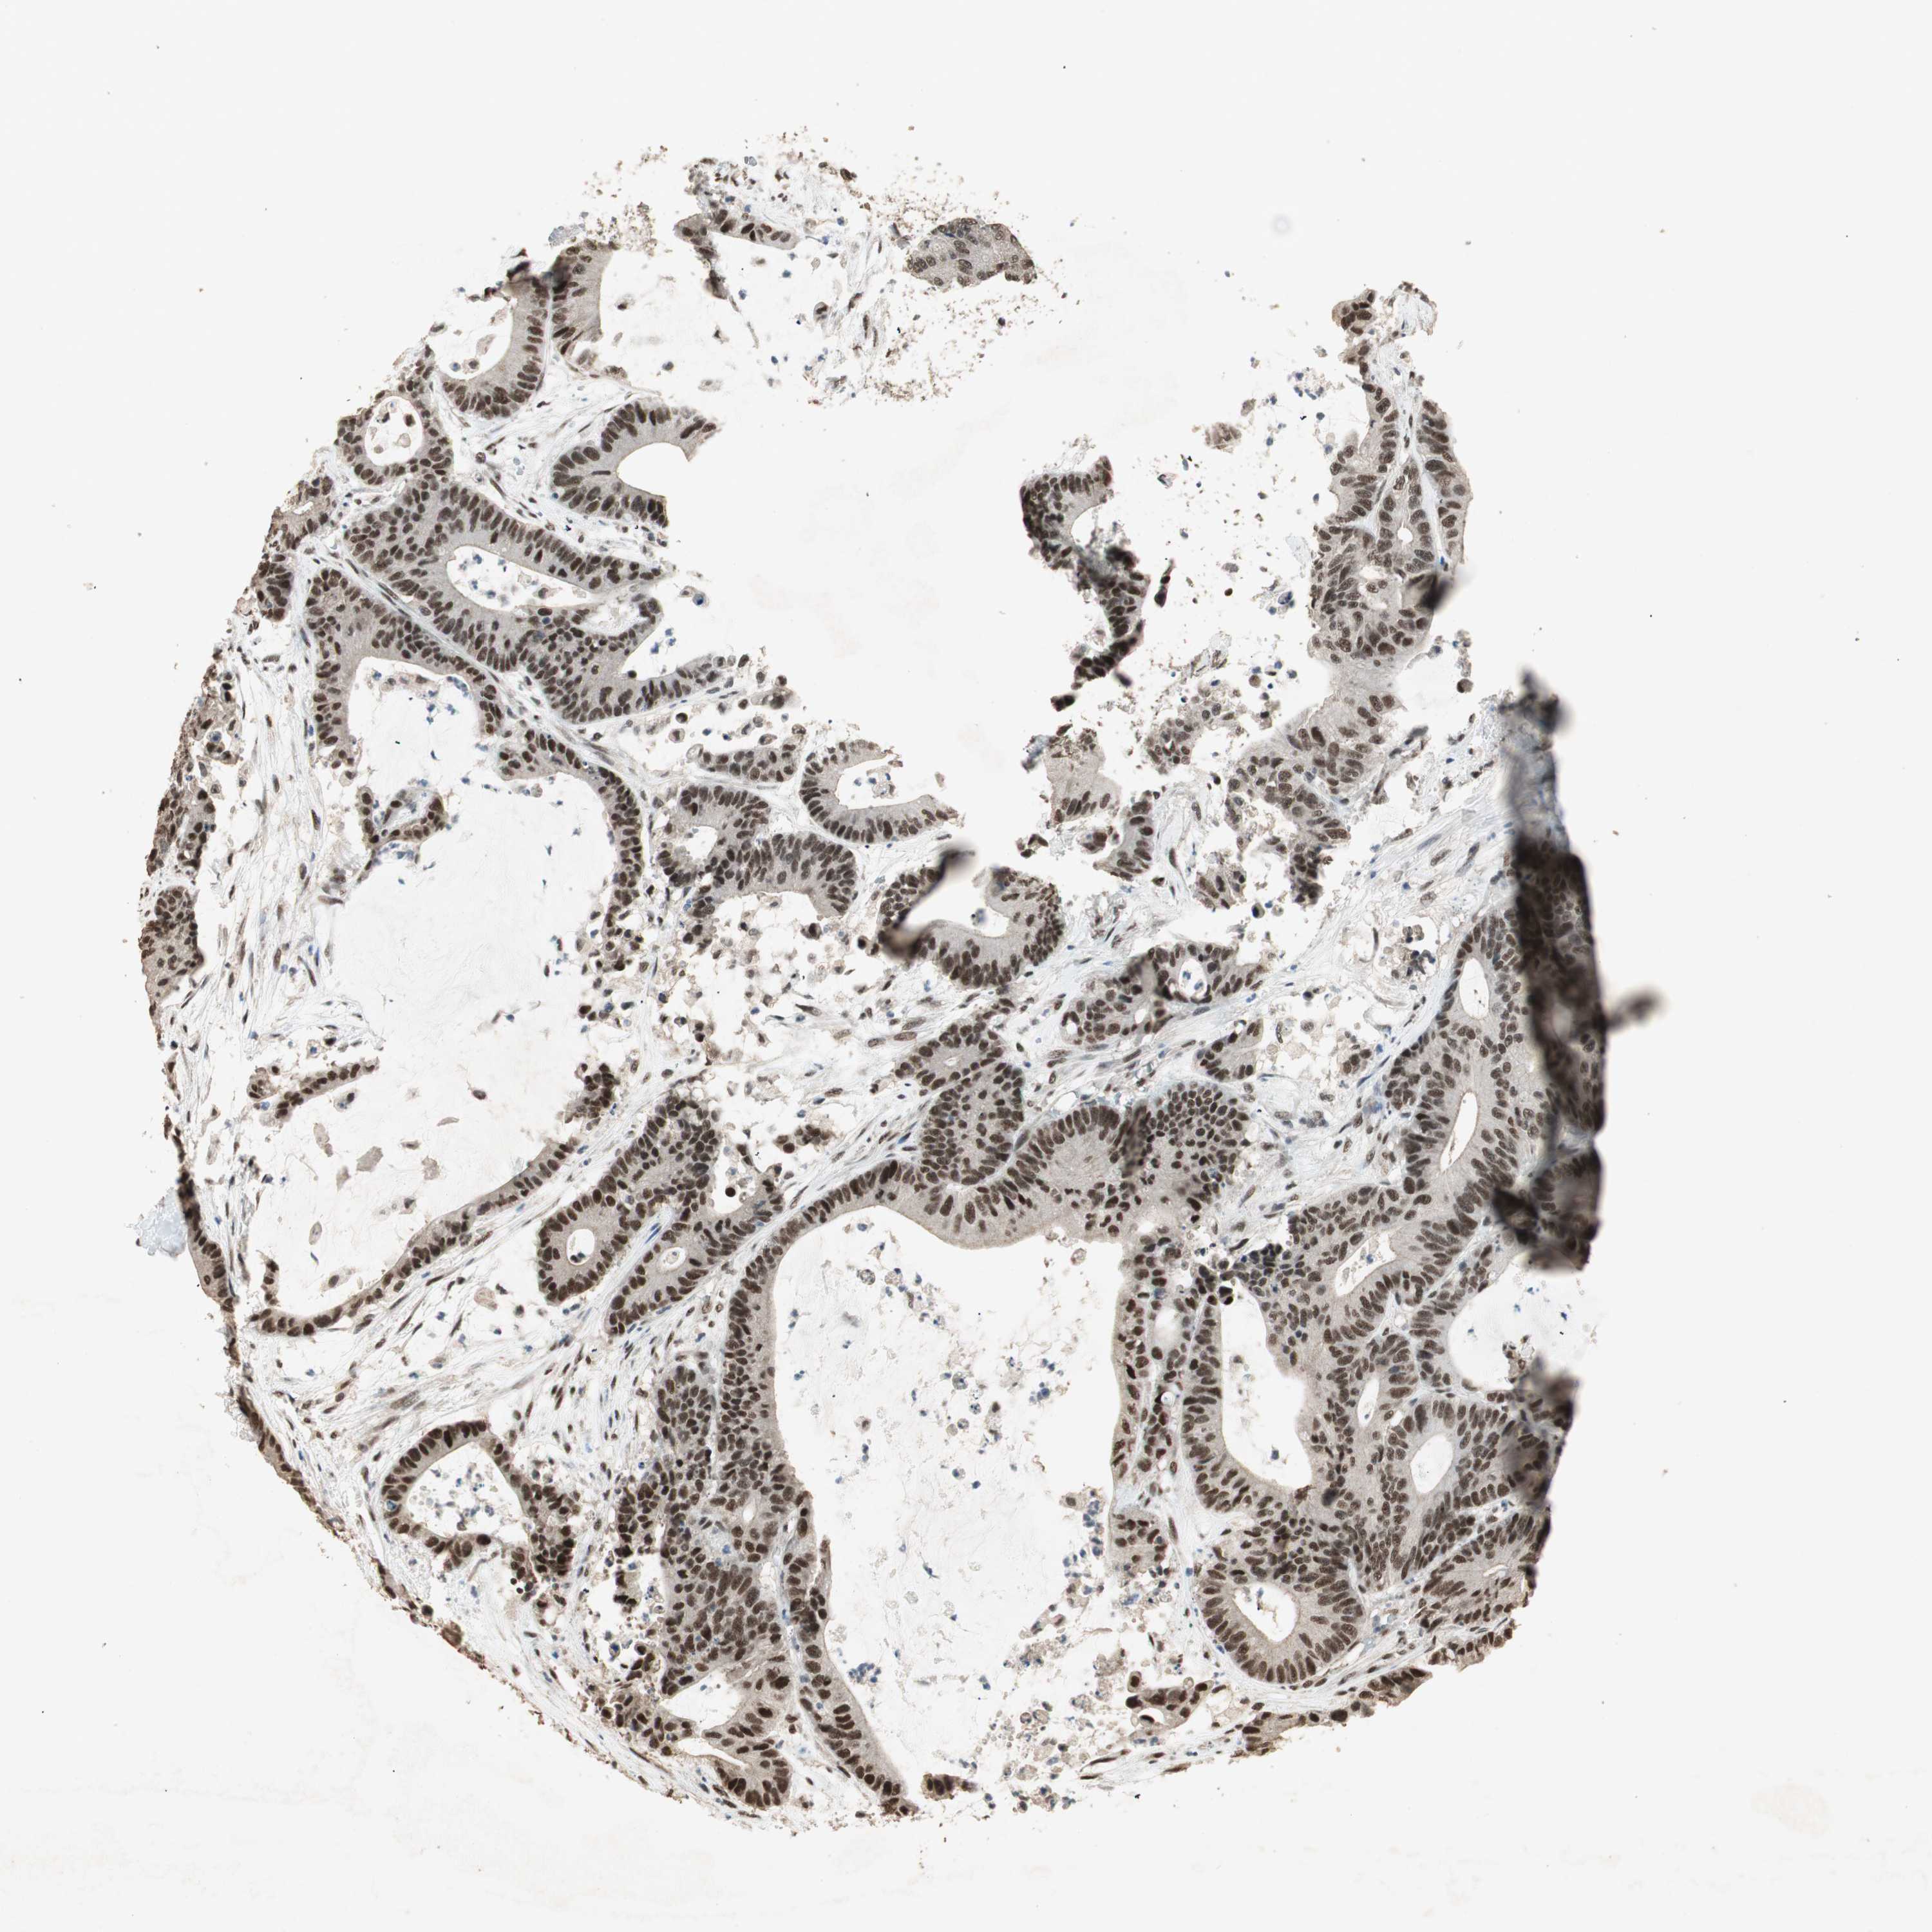

CANCER COLORECTAL CANCER Show tissue menu

Colorectal cancer

Colon adenocarcinoma